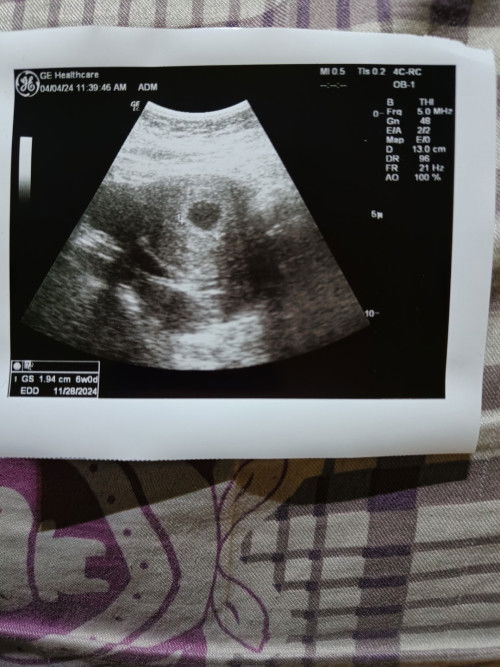

Kantong janin 6 weeks

Bunda mau tanya, klo dokternya cuma bilang selamat ada tanda kehamilan muda terlihat kantong kehamilannya Diusia 6 weeks gpp ya bun blum keliatan janin? Ini usg 2 dimensi #newmom #bantusharing #6minggu